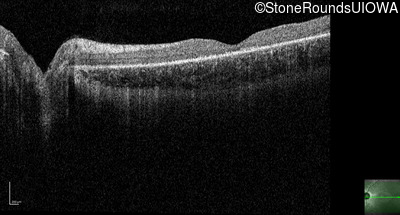

Optical Coherence Tomography - Right - 10/200

Exemplar / OCT Stack